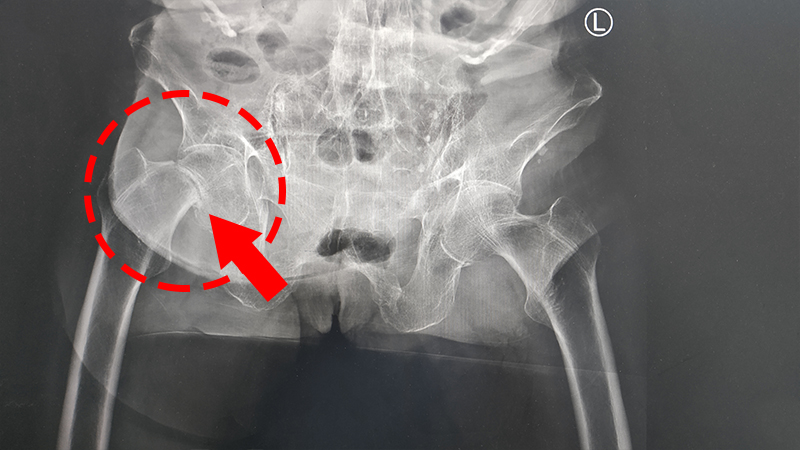

医师通过骨盆X片见:吴婆婆右股骨颈骨折,骨折端移位明显,诊断为“右股骨颈骨折”。

之后在我院进行了“右侧人工股骨头置换术”,手术非常顺利,术后髋关节也比较稳定,髋关节高度及各角度测量良好,假体活动自如,后在崔医生以及骨一科全体医护人员的精心照料下康复出院啦。